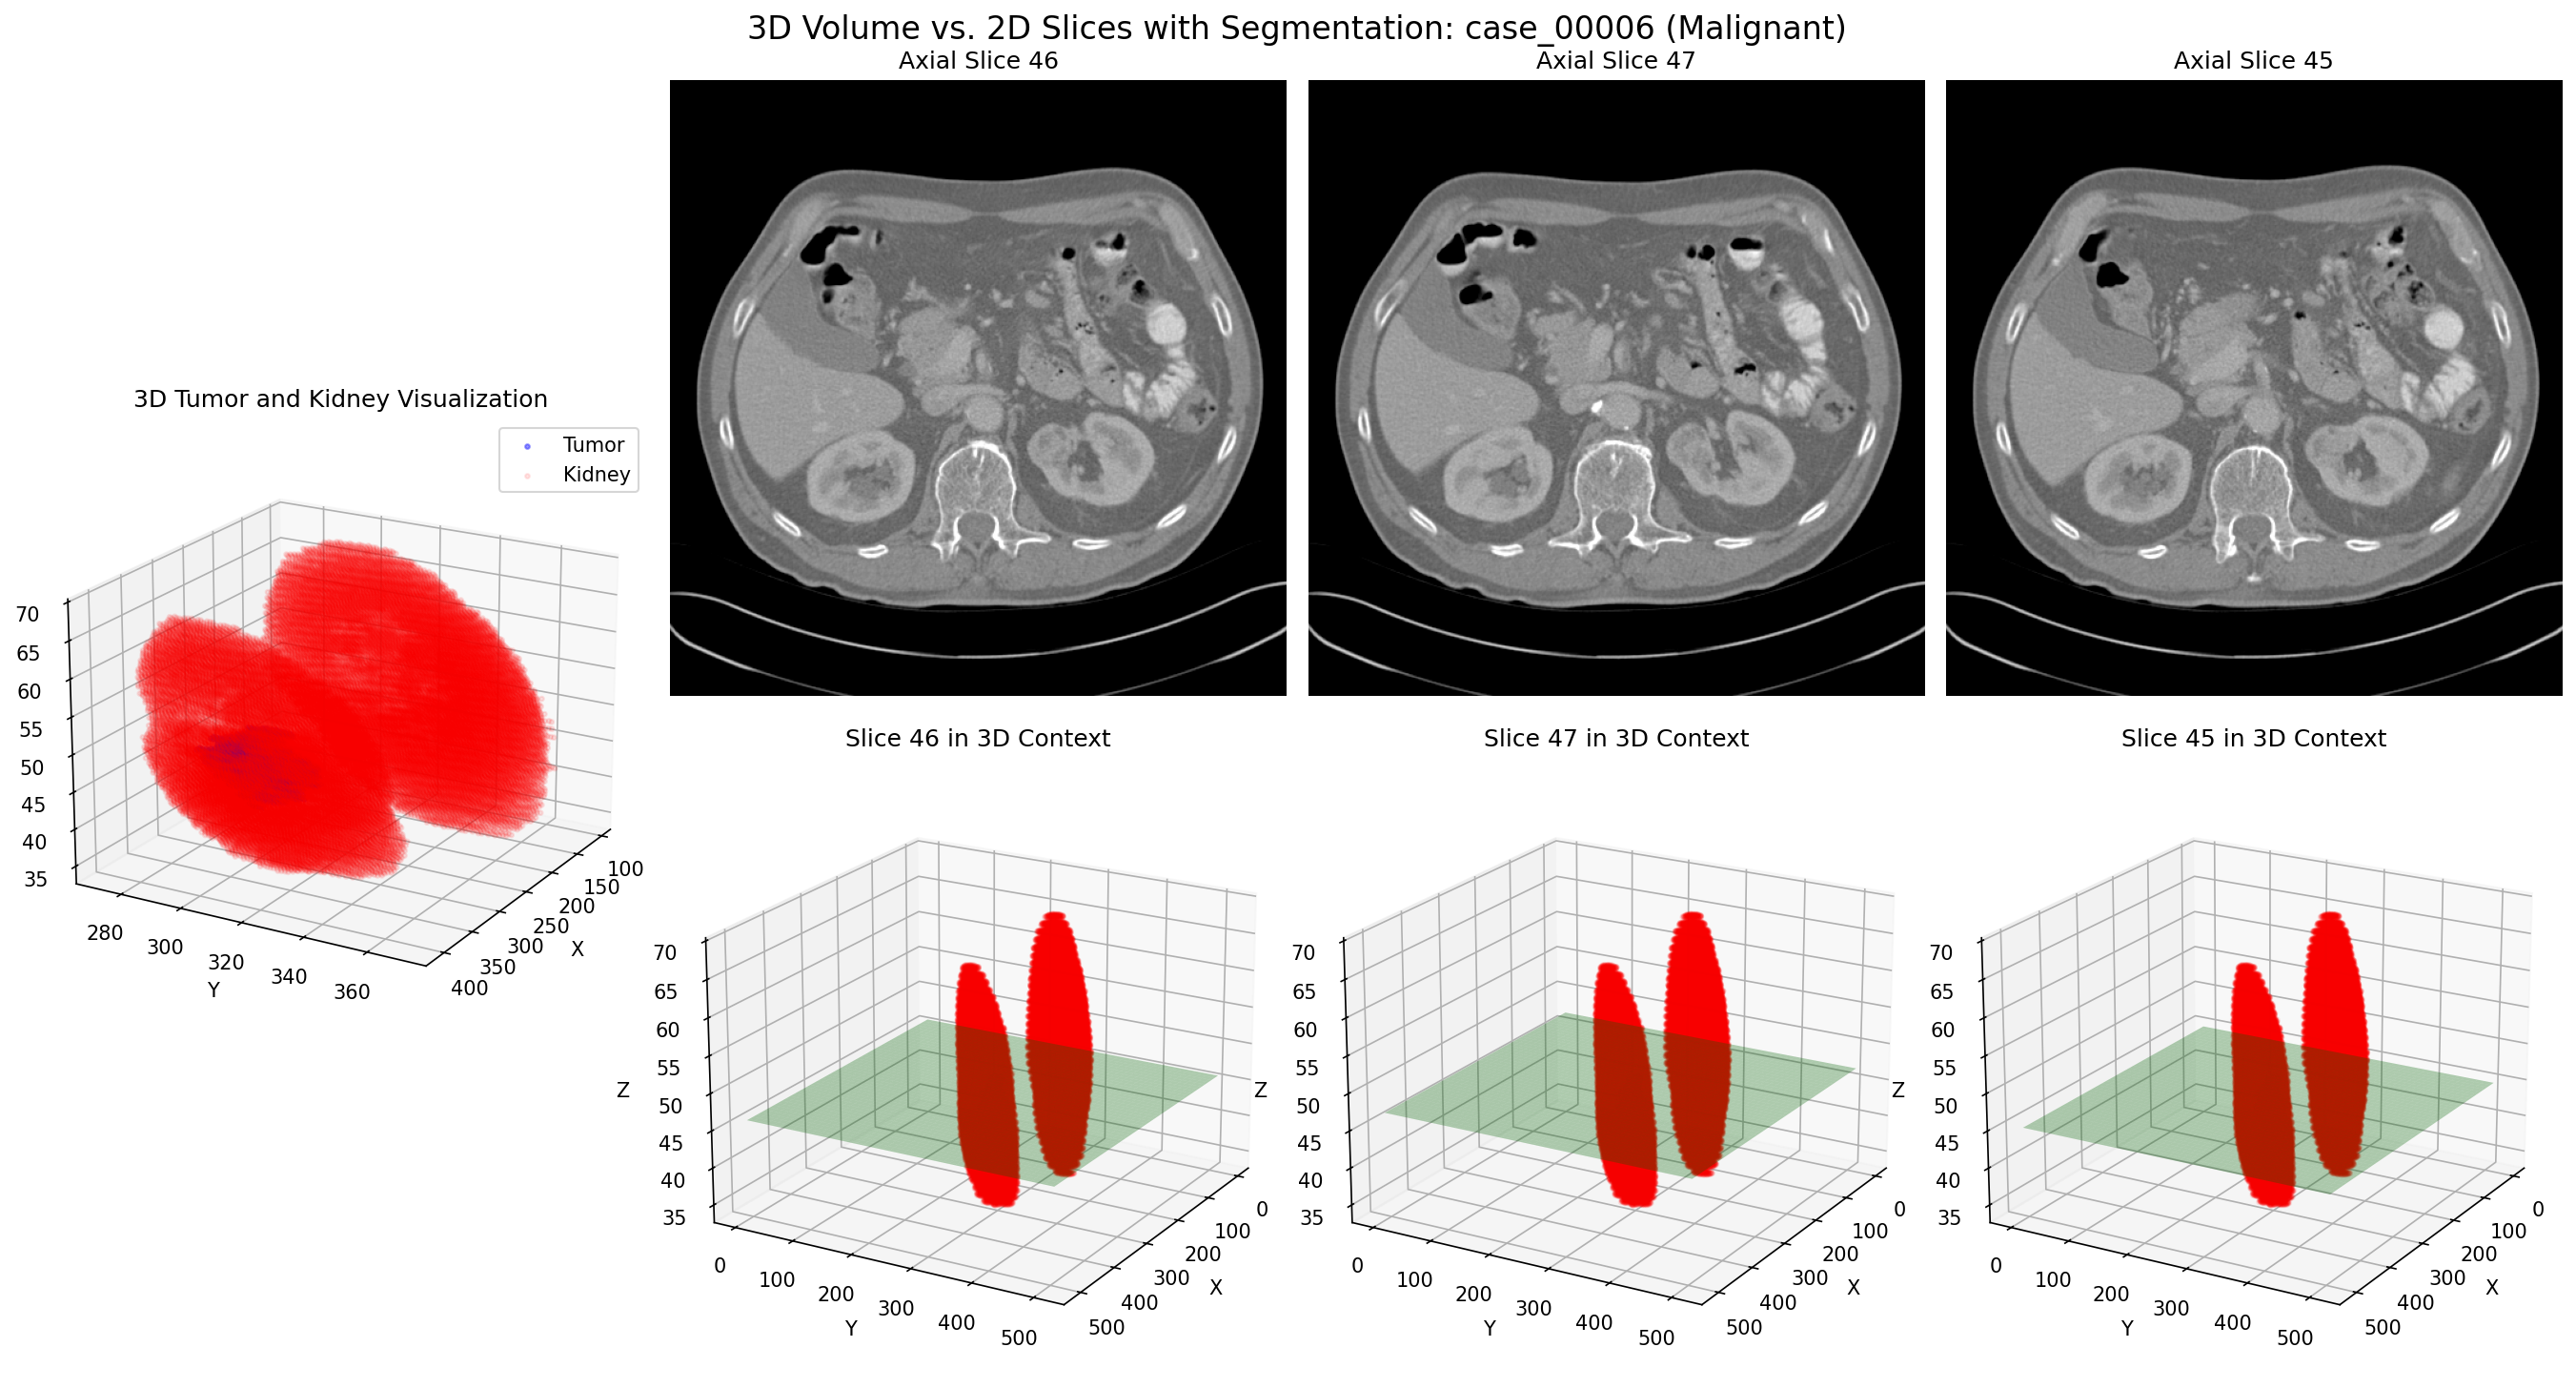

The diagram to the right illustrates how our approach extracts the most relevant 2D slices from a 3D volume, optimizing both the quantity and quality of training data.

Diagram showing how 3D volumetric data is transformed into multiple 2D slices along different planes for optimal model training

Case 00006: 3D volume (top row) and corresponding 2D slices (bottom row) of a malignant kidney tumor

Case 00006: Malignant Tumor

These side-by-side comparisons show the relationship between 3D tumor volumes (top row) and their corresponding 2D slices (bottom row) for both malignant and benign cases. Our algorithm intelligently selects the most informative 2D slices from each 3D volume, capturing the key diagnostic features while generating multiple training examples from a single case.

Key insight: By converting each 3D case into multiple 2D slices, we effectively increased our training data by a factor of 8-10, with each slice carrying distinct morphological information about the tumor.